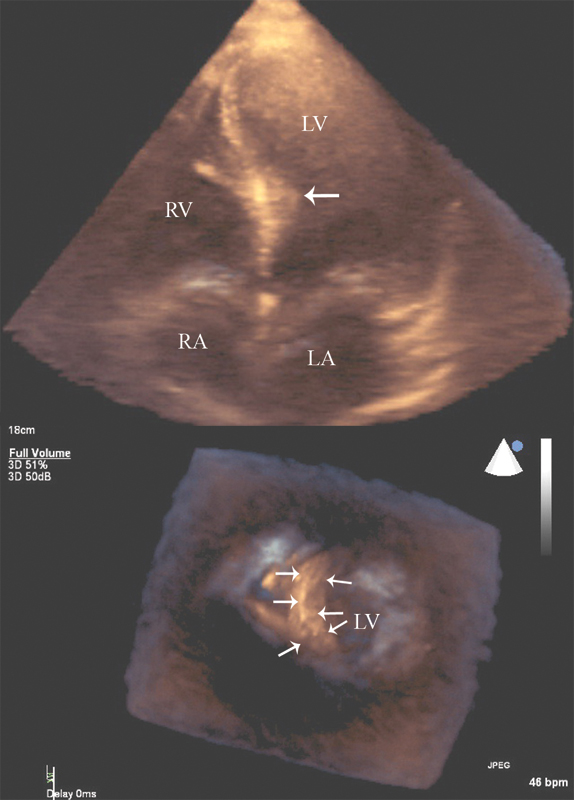

فحوصات تشخيصية لبعض امراض القلب والشرايين التاجية